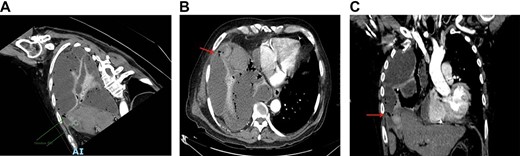

A thoracentesis was performed in the right hemithorax with an outflow of 1000 cc of cloudy, nonfetid yellow pleural fluid with Light criteria for exudate. Therefore, pleural tube placement is considered in the patient. Pathology reports the fluid drained had a pH of 8.5, white blood cell count of 470 cu/mm3 with 67% polymorphonuclear cells, total bilirrubin 4.2 mg/dl, and direct bilirrubin 1.1 md/dl. A contrasted chest tomography (Fig. 1A–C) was performed with an extension to the upper abdomen, where a perforated cholecystolithiasis was reported with a probable cholecystopleural fistula forming an empyema with a volume of 3244 cc. A right chest tube was placed, and a laparoscopic cholecystectomy was scheduled plus closure of the cholecystopleural fistula. Later, the gallbladder was sent to the department of pathology to rule out any probable cancer, obtaining a negative result for neoplasia.

(A) Cholecystopleural fistula by contrast-enhanced thoracic CT. (B) Axial view that shows the perforation of the funds of the gallbladder with disruption of the right hemidiaphragm. (C) Coronal view that shows the perforation of the funds of the gallbladder with disruption of the right hemidiaphragm.